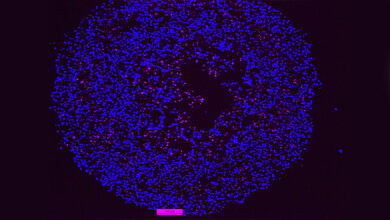

Forscher analysierten Darmkrebsproben und suchten nach Proteinen, die in den Tumorzellen, nicht aber im gesunden Gewebe vorkommen. Zwei Proteine weckten ihr Interesse. B7H3 und B7H4 waren in großer Zahl in Darmkrebszellen vorhanden, während sie im gesunden Gewebe fast nicht nachweisbar waren.

„Wir beschlossen, B7H3 und B7H4 in Darmkrebszellen zu blockieren“, sagt Dr. Peuker. „Das Ergebnis war verblüffend. Tumorgewebe, in dem diese Signale ausgeschaltet waren, wuchs deutlich langsamer oder schrumpfte sogar. Wir konnten beobachten, dass die Immunzellen nun in das Krebsgewebe eindringen konnten und begannen, die Tumorzellen zu kontrollieren.“ Weitere Tests bestätigten, dass die Proteine B7H3 und B7H4 tatsächlich als Checkpoint-Proteine funktionieren. „Durch die Blockierung dieser Signale konnte das Immunsystem plötzlich Tumorzellen angreifen“, fügt Prof. Zeißig hinzu.

Das Team charakterisierte eine breite Kaskade von Ereignissen, die es dem Darmkrebs ermöglichen, seine Fähigkeit zur Blockierung von Immunzellen zu entwickeln. Sie konnten zeigen, dass die Durchbrechung der Darmbarriere ein entscheidender Schritt in diesem Prozess ist. Wenn die Darmbarriere an den Stellen der Tumorentwicklung durchbrochen wird, können Bakterien, die normalerweise im Darm vorhanden sind, plötzlich in das umliegende Gewebe eindringen. Dies gilt als wichtiges frühes Ereignis bei der Entstehung von Darmkrebs. Nun konnte das Team von Prof. Zeißig zeigen, dass diese bakteriellen Ausreißer den Darmkrebszellen als Auslöser dienen, um sich vor dem Immunsystem zu verstecken.

„Wir haben festgestellt, dass die im Gewebe vorhandenen Zellen die eindringenden Bakterien erkennen können. Dies wiederum setzt eine ganze Kaskade von Schritten in Gang. Die daraus resultierende molekulare Kommunikation zwischen den Zellen führt schließlich dazu, dass die Krebszellen B7H3 und B7H4 auf ihrer Oberfläche ausbilden und sich vor dem Immunsystem verstecken“, sagt Dr. Peuker.